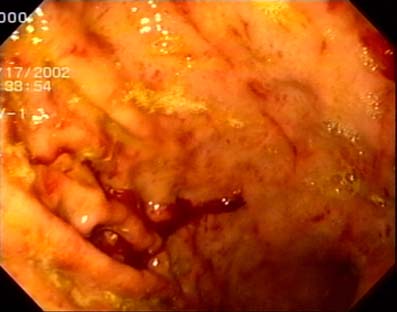

Efeitos da gastrite podem ser reduzidos com boa alimentação

A gastrite é um processo inflamatório da parede do estômago, que ode ser aguda ou crônica, quando dura meses a anos. Normalmente é causada por fatores como uso exagerado de medicamentos com ácido acetilsalicílico, anti-inflamatórios, infecção por salmonela, álcool em excesso e bactérias.